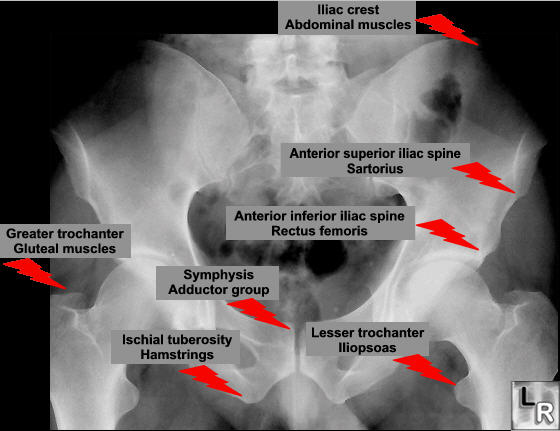

Any of the major muscle attaching to the pelvis or proximal femur may pull off at their attachment. This is classically a sporting injury, resulting from those resulting from extreme, unbalanced, often eccentric muscular contractions.

Once healing starts these lesions may mimic the appearance of an osteosarcoma, unfortunately so may the histology.

Ischial Avulsion

This can mimic a simple hamstring strain, although there is usually more bruising. Most patients are treated conservatively. If the displacement is more than 2 cm then internal fixation is indicated.

Anterior-Superior Iliac Spine Avulsion

This is the attachment of the sartorius and tensor fascia lata muscles.